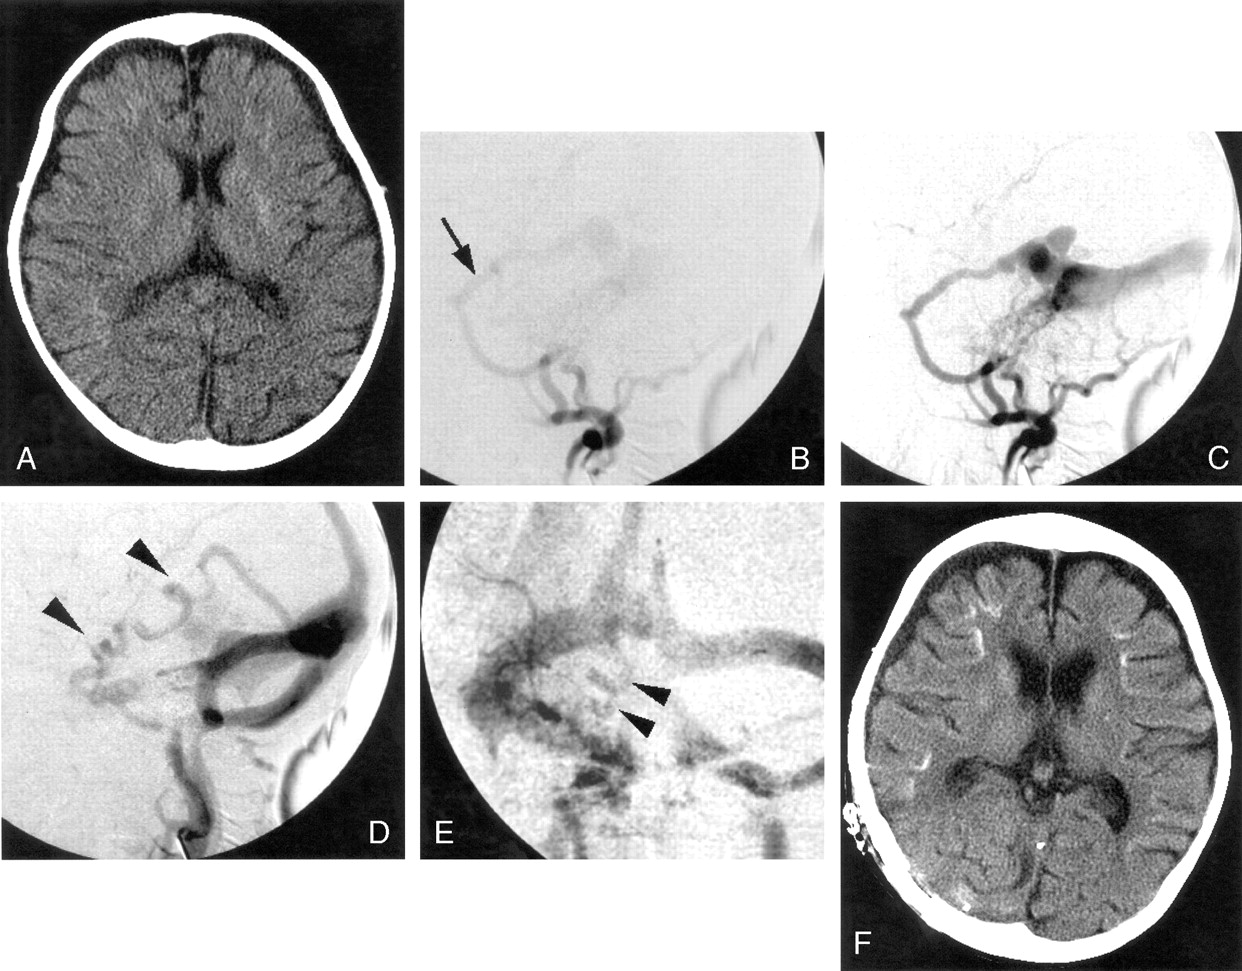

Case 3.

A, CT scans shows diffuse atrophy and subtle calcification in the basal ganglia and subcortical region at the bottom of cerebral gyri bilaterally. The subcortical calcification was curvilinear and predominant on the right side.

B–E, Right external carotid angiograms (B–D, lateral projection; E, frontal projection) show dAVF fed by the enlarged middle meningeal (arrow) and ascending pharyngeal arteries with cortical venous reflux (arrowheads).

F, Repeated CT scans after 1 year reveal a more advanced degree of diffuse atrophy and denser subcortical calcification.

By means of transvenous embolization, arteriovenous shunt was partially resolved with partial disappearance of CVR, and her symptom of convulsion became controllable. Approximately 1 year after the initial embolization, she developed uncontrollable convulsion again, and repeat CT showed advanced degree of diffuse atrophy and denser subcortical calcification. She underwent transarterial re-embolization immediately followed by surgical isolation of the right transverse sinus and remains free of convulsion.